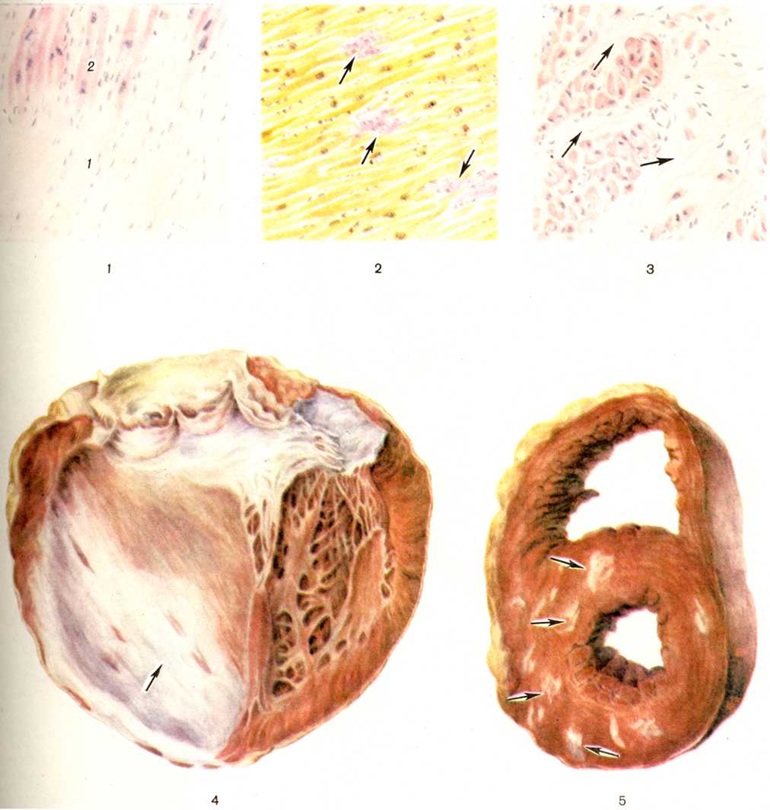

КардиосклерозКардиосклероз (греческий kardia сердце + sklerosis уплотнение; синонимы: миокардиосклероз, миофиброз, склероз сердца, фиброз сердца) — разрастание соединительной ткани в сердечной мышце, наступающее обычно вслед за гибелью мышечных волокон или параллельно ей. Кардиосклероз, как правило, процесс вторичный, является исходом различных по своей этиологии и патогенезу процессов в миокарде. Кардиосклероз может быть проявлением ишемической болезни сердца (смотри полный свод знаний). Первичный Кардиосклероз встречается крайне редко. Морфологически различают постинфарктный Кардиосклероз, заместительный Кардиосклероз, миокардитический Кардиосклероз и Кардиосклероз вследствие кардиомиопатий (смотри полный свод знаний) различной этиологии; Кардиосклероз развивается также при базедовой болезни. Постинфарктный кардиосклероз (крупноочаговый Кардиосклероз, мозоль миокарда, рассеянный очаговый Кардиосклероз, постинфарктный рубец) возникает вследствие нарушения коронарного кровообращения, приводящего к инфаркту миокарда (смотри полный свод знаний) как проявлению ишемической болезни сердца. Значительно реже постинфарктный Кардиосклероз является следствием некроза участка миокарда в результате эмболии венечных артерий тромботическими массами при эндокардите митрального клапана или пристеночных тромбах в левой половине сердца; поражения ветвей коронарных артерий при ревматизме или артериитах различной природы (например, при генерализованном неспецифическом артериите, или болезни Такаясу, нодозном панартериите), при сужении их устьев в результате сифилитического мезаортита, стенозе аортального отверстия при сифилитическом пороке сердца или при изолированном кальцинозе аортальных клапанов. По-видимому, следствием эмболии является также крупноочаговый Кардиосклероз, наблюдающийся избирательно в области верхушки сердца при кардиомегалиях, связанных с болезнью Шагаса, и при идиопатической гипертрофии сердца, сопровождающихся, как правило, образованием пристеночных тромбов в левом желудочке сердца. Формирование Кардиосклероз при крупноочаговом инфаркте миокарда происходит путём замещения погибшего участка мышцы сердца молодой соединительной тканью. Погибшие мышечные волокна подвергаются коагуляции и последующему распаду сначала с участием лейкоцитов, а затем макрофагов, поглощающих продукты распада. Одновременно происходит размножение фибробластов, новообразование капилляров, тонкостенных синусоидальных сосудов из сохранившихся участков стромы, особенно вокруг сосудов, накопление гликозаминогликанов и формирование молодой соединительной ткани с образованием сети аргирофильных и коллагеновых волокон. Количество коллагеновых волокон по мере созревания соединительной ткани увеличивается, они приобретают упорядоченное расположение параллельно друг другу, количество гликозаминогликанов и клеточных элементов уменьшается, часть сосудов запустевает и образуется плотный соединительнотканный рубец (цветной таблица, ст. 144, рисунок 1) с небольшим количеством клеточных элементов и сосудов, иногда в дальнейшем с отложением солей извести. Эластические волокна в рубце представлены то очень скудно в виде отдельных беспорядочно расположенных волоконец, то в большом количестве в виде густых сетей, расположенных между пучками коллагеновых волокон. Иногда в рубец, особенно по периферии или вокруг сохранившихся интрамуральных артерий, могут быть включены небольшие группы сохранившихся миокардиальных клеток, часто с различными проявлениями дистрофических изменений. В полях постинфарктного Кардиосклероз после обширных инфарктов в центре иногда в течение длительного времени сохраняются участки некротизированного миокарда. Заживление мелкоочаговых инфарктов миокарда протекает аналогичным образом, отличаясь лишь размерами образовавшегося рубца и скоростью его формирования. Постинфарктный Кардиосклероз соответственно размерам перенесённого инфаркта может захватывать всю толщу миокарда или отдельные его слои; после повторных инфарктов могут наблюдаться обширные рубцы разной локализации, протяжённости, изолированные или смыкающиеся друг с другом. Наиболее частой локализацией Кардиосклероз являются верхушка сердца, передняя, несколько реже задняя стенка левого желудочка, межжелудочковая перегородка, папиллярные мышцы. Постинфарктный Кардиосклероз правого желудочка в ряде случаев наблюдается одновременно с постинфарктным Кардиосклероз левого желудочка, обычно являясь продолжением изменений в левом желудочке. Изолированное поражение правого желудочка наблюдается очень редко. Постинфарктный Кардиосклероз предсердий обнаруживается, как правило, одновременно с рубцовыми изменениями в левом желудочке, но обычно не является их продолжением; изолированный постинфарктный Кардиосклероз предсердий встречается редко. |

Сердце при постинфарктном Кардиосклероз увеличено, полости его расширены; на разрезе в стенке видны белесоватые поля соединительной ткани различной протяжённости и формы. В зависимости от размеров инфаркта они могут иметь вид прослоек или распространяться на всю толщу миокарда — так называемый мозоль миокарда (цветной рисунок 4). В последнем случае стенка желудочка истончена, кожистого вида, иногда вследствие отложения солей извести хрустит при разрезе. В результате истончения стенки образуется так называемый внутренняя аневризма сердца, не изменяющая его наружных контуров. Рубцовые поля лишены сократительной способности и под влиянием систолического давления в дальнейшем могут подвергаться растяжению с образованием аневризм («наружная аневризма»), размеры которых могут варьировать в широких пределах. Полость аневризм часто выполнена тромботическими наложениями, могущими служить источником эмболий. После субэндокардиальных инфарктов миокарда развивается Кардиосклероз, локализующийся непосредственно под эндокардом. При обширных поражениях такого рода полость левого желудочка на большом протяжении оказывается как бы окружённой футляром из рубцовой ткани, со склерозом трабекулярных мышц, запустеванием межтрабекулярных пространств и облитерацией устьев наименьших вен сердца (тебезиевы вены). Мелкоочаговые инфаркты миокарда ведут к образованию рубцов, число, размеры и локализация которых могут варьировать в широких пределах — так называемый рассеянный очаговый Кардиосклероз (цветной рисунок 5). Он может образовываться также в исходе повреждений миокарда, обычно сопровождающихся лизисом мышечных клеток и коллапсом стромы с последующим гиалинозом при минимальном размножении стромальных клеточных элементов.

При гипертонической болезни исходным моментом развития Кардиосклероз является гиперплазия, содружественная с гипертрофией миокарда, и огрубение аргирофильного каркаса стромы (рисунок 1); в дальнейшем происходит формирование коллагеновых волокон и развитие диффузного миофиброза. Характерным для этого вида Кардиосклероз является также наличие в миокарде микроскопических рубчиков (цветной рисунок 2) вследствие гибели отдельных миоцитов или небольших групп их.

Миокардитический кардиосклероз — исход миокардитов (смотри полный свод знаний) инфекционно-аллергической, бактериальной или вирусной этиологии, сопровождающихся экссудативными и пролиферативными процессами в строме миокарда и деструктивными изменениями миоцитов. К этим процессам относится Кардиосклероз после перенесённого ревматизма, дифтерии, скарлатины, заражения Коксаки-вирусом или энцефаломиокардитическим вирусом, изредка вирусом полиомиелита или оспенной вакцинации; чрезвычайной редкостью является Кардиосклероз после туберкулёзного или сифилитического интерстициального миокардита. Миокардитический Кардиосклероз может носить характер диффузного миофиброза, локализующегося преимущественно в левом желудочке, и выражается в распространённом огрубении аргирофильной стромы миокарда и образовании коллагеновых волокон, что придаёт строме вид грубой решётки, в ячейках которой заключены отдельные мышечные волокна или группы их. Такой Кардиосклероз называют стромогенным. В случае же гибели небольших групп миоцитов возникают небольшие рубчики, или очажки Кардиосклероз. При диффузном ревматическом интерстициальном миокардите с мукоидной дезорганизацией стромы наблюдается диффузный интерстициальный миофиброз (цветной таблица, ст. 144, рисунок 3) и одновременно как исход ревматических гранулем около сосудов возникают овальные или звездчатые рубчики, являющиеся важным диагностическим признаком ревматизма (рисунок 2). Кардиосклероз (диффузный миофиброз) наблюдается также после аллергических миокардитов неясной этиологии (миокардита Фидлера, аллергического миокардита, описанного Я. Л. Рапопортом).